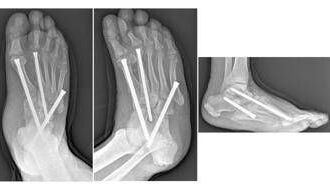

Piede di Charcot, al Gemelli soluzioni avanzate per una complicanza rara del diabete

(Adnkronos) - Uno dei più temibili nemici del piede è una grave…